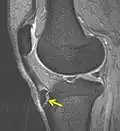

Une radiographie n'est pas nécessaire notamment lorsque le tableau clinique est évocateur et que les douleurs sont bilatérales. Elle peut être utile pour éliminer une autre pathologie si les douleurs sont unilatérales, atypiques ou rebelles au traitement. Initialement on retrouve un soulèvement de la tubérosité tibiale antérieure avec élargissement de son cartilage de croissance ; dans les stades plus évolués, la TTA est fragmentée et on peut voir parfois des calcifications dans le ligament rotulien[2].

IRM d'un Osgood-Schlatter- Radiographie d'un Osgood-Schlatter